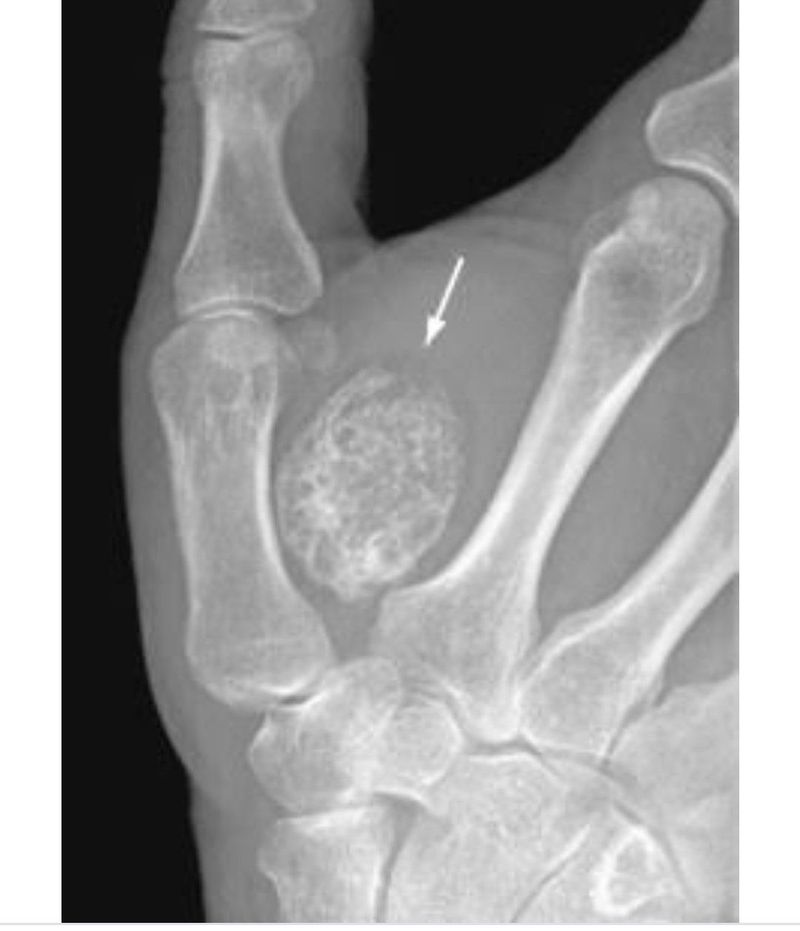

Myositis ossificans